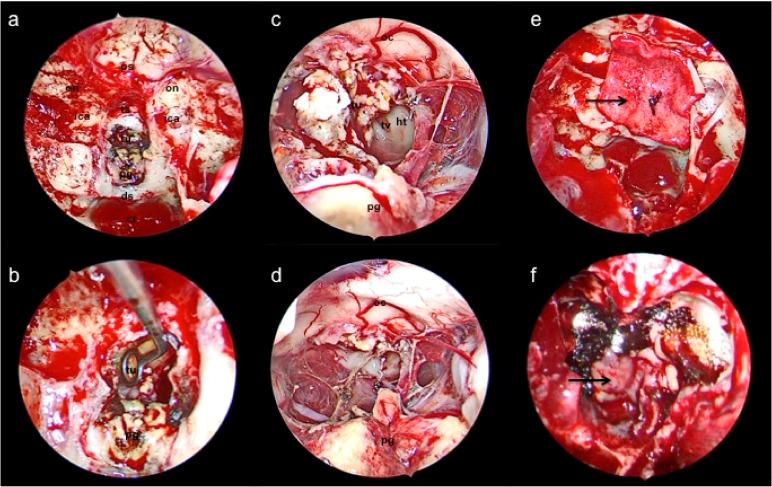

Craniopharyngiomas are rare, benign primary brain tumors that arise from remnants of the craniopharyngeal duct epithelium within the sellar and suprasellar region. Despite their benign biology, they may cause significant morbidity, secondary to involvement of nearby eloquent neural structures, such as the pituitary gland, hypothalamus, and optic apparatus. Historically, aggressive surgical resection was the treatment goal to minimize risk of tumor recurrence via open transcranial midline, anterolateral, and lateral approaches, but could lead to clinical sequela of visual, endocrine, and hypothalamic dysfunction. However, recent advances in the endoscopic endonasal approach over the last decade have mostly supplanted transcranial surgery as the optimal surgical approach for these tumors. With viable options for adjuvant radiation therapy, targeted medical treatment, and alternative minimally invasive surgical approaches, the management paradigm for craniopharyngiomas has shifted from aggressive open resection to more minimally invasive but maximally safe resection, emphasizing quality of life issues, particularly in regards to visual, endocrine, and hypothalamic function. This review provides an update on current multi-modal approaches for craniopharyngiomas, highlighting the modern surgical treatment paradigm for this disease entity.